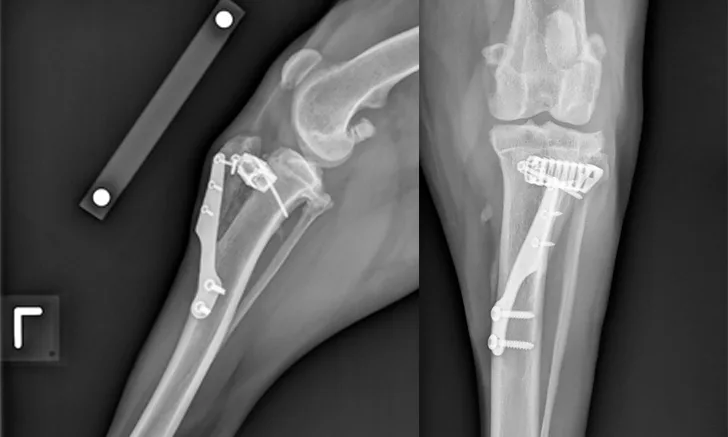

Mild discomfort and crepitus can be noted on passive range of motion of the left stifle. There is positive cranial drawer but negative cranial tibial thrust of the left stifle. There is mild effusion of the right stifle joint; otherwise, no pain, instability, or limitations on passive range of motion are appreciated. The dog is sedated, and radiographs of the left stifle joint are obtained (Figure 1).

Two x-ray views of stifle joint with orthopedic hardware in place.

FIGURE 1

Orthogonal radiographs of the left stifle joint 6 weeks after tibial tuberosity advancement.